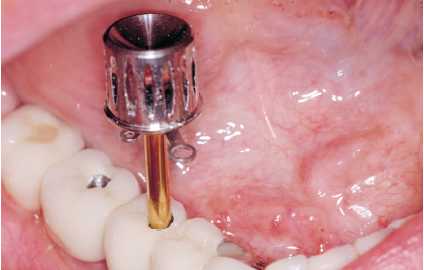

Figuras 2a y 2b. Adiestramiento en la clínica con el

paciente de la utilización de superflos y cepillos interproximales